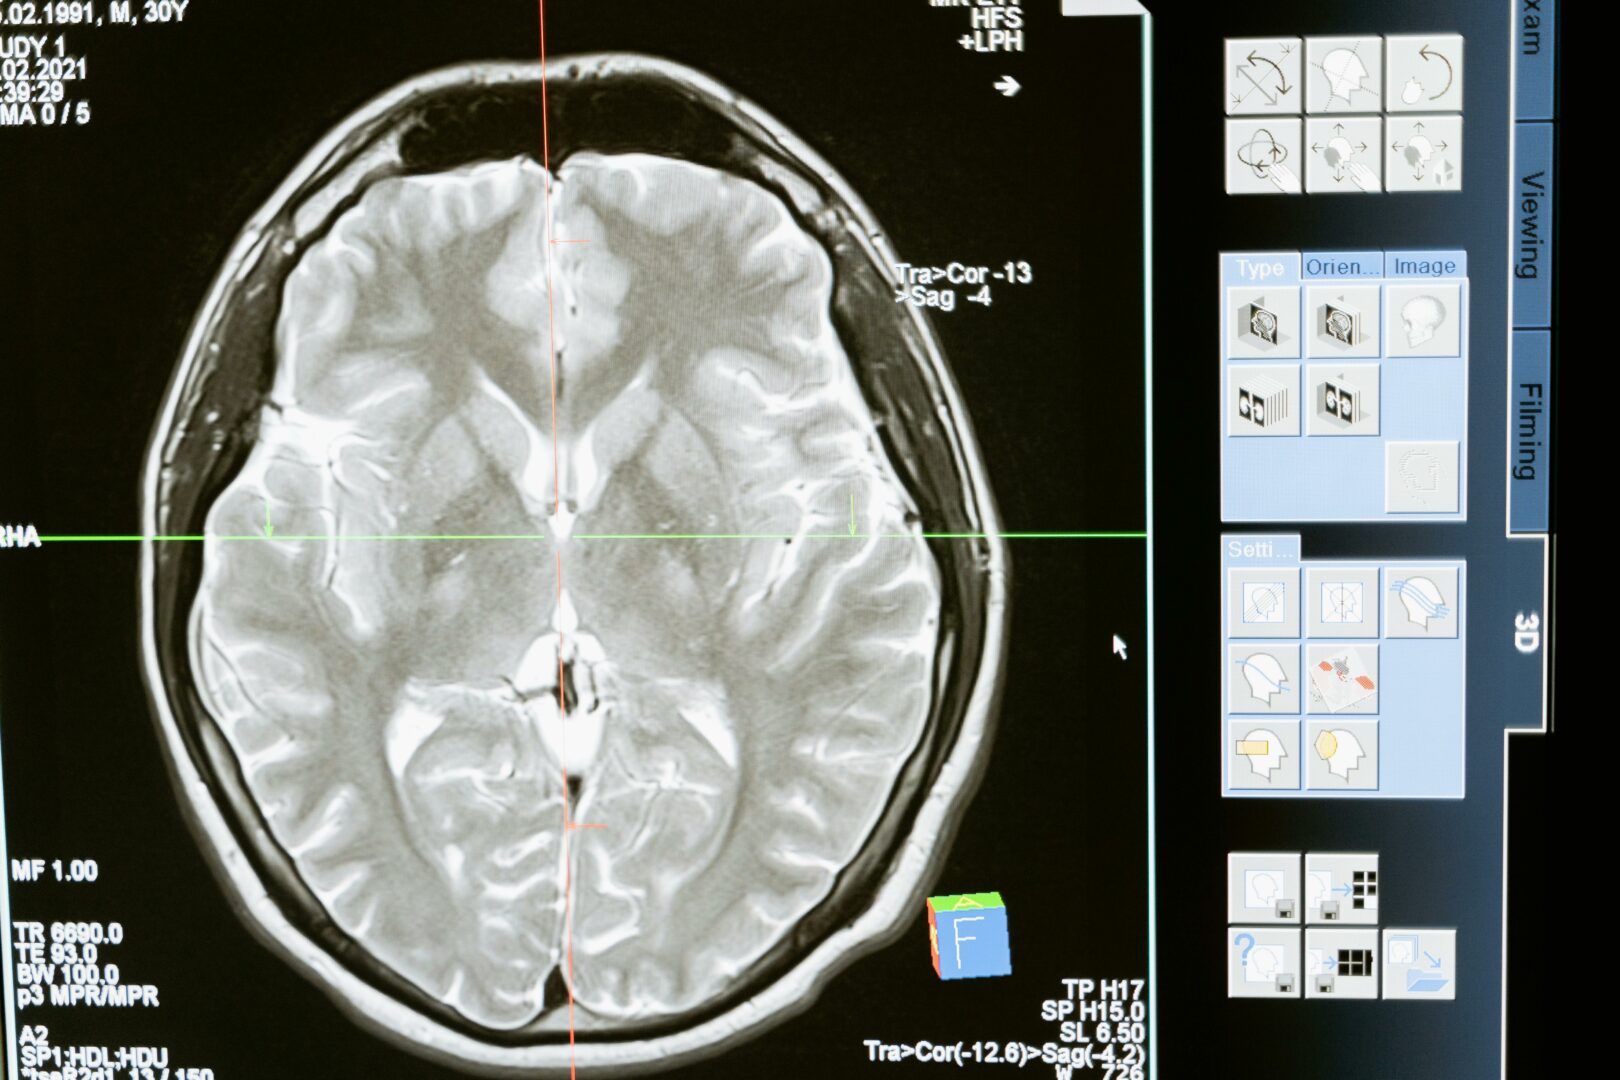

Aivojen magneettikuva. / Mart Production